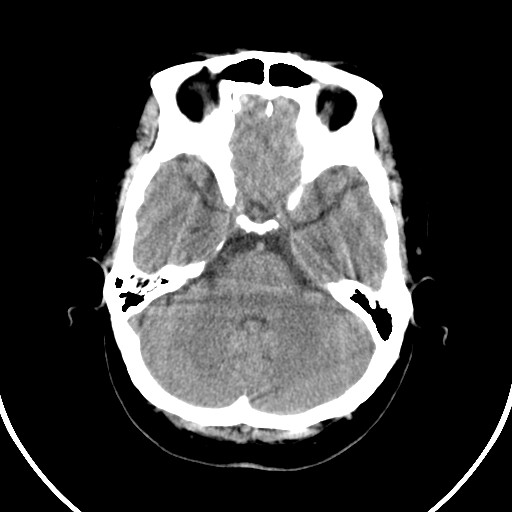

女,56岁,右中指淤肿,右手麻痹1天

右枕叶低密度区伴硬膜下血肿——增强扫描或mri。

双侧侧脑室额角旁对称性略低密度影,边缘模糊,无占位效应,考虑轻度脑白质稀疏症(病人有高血压吗).,右枕叶低密度影多为伪影,不放心薄扫一下.

右枕叶条状低密度影不应该忽略可能极具意义